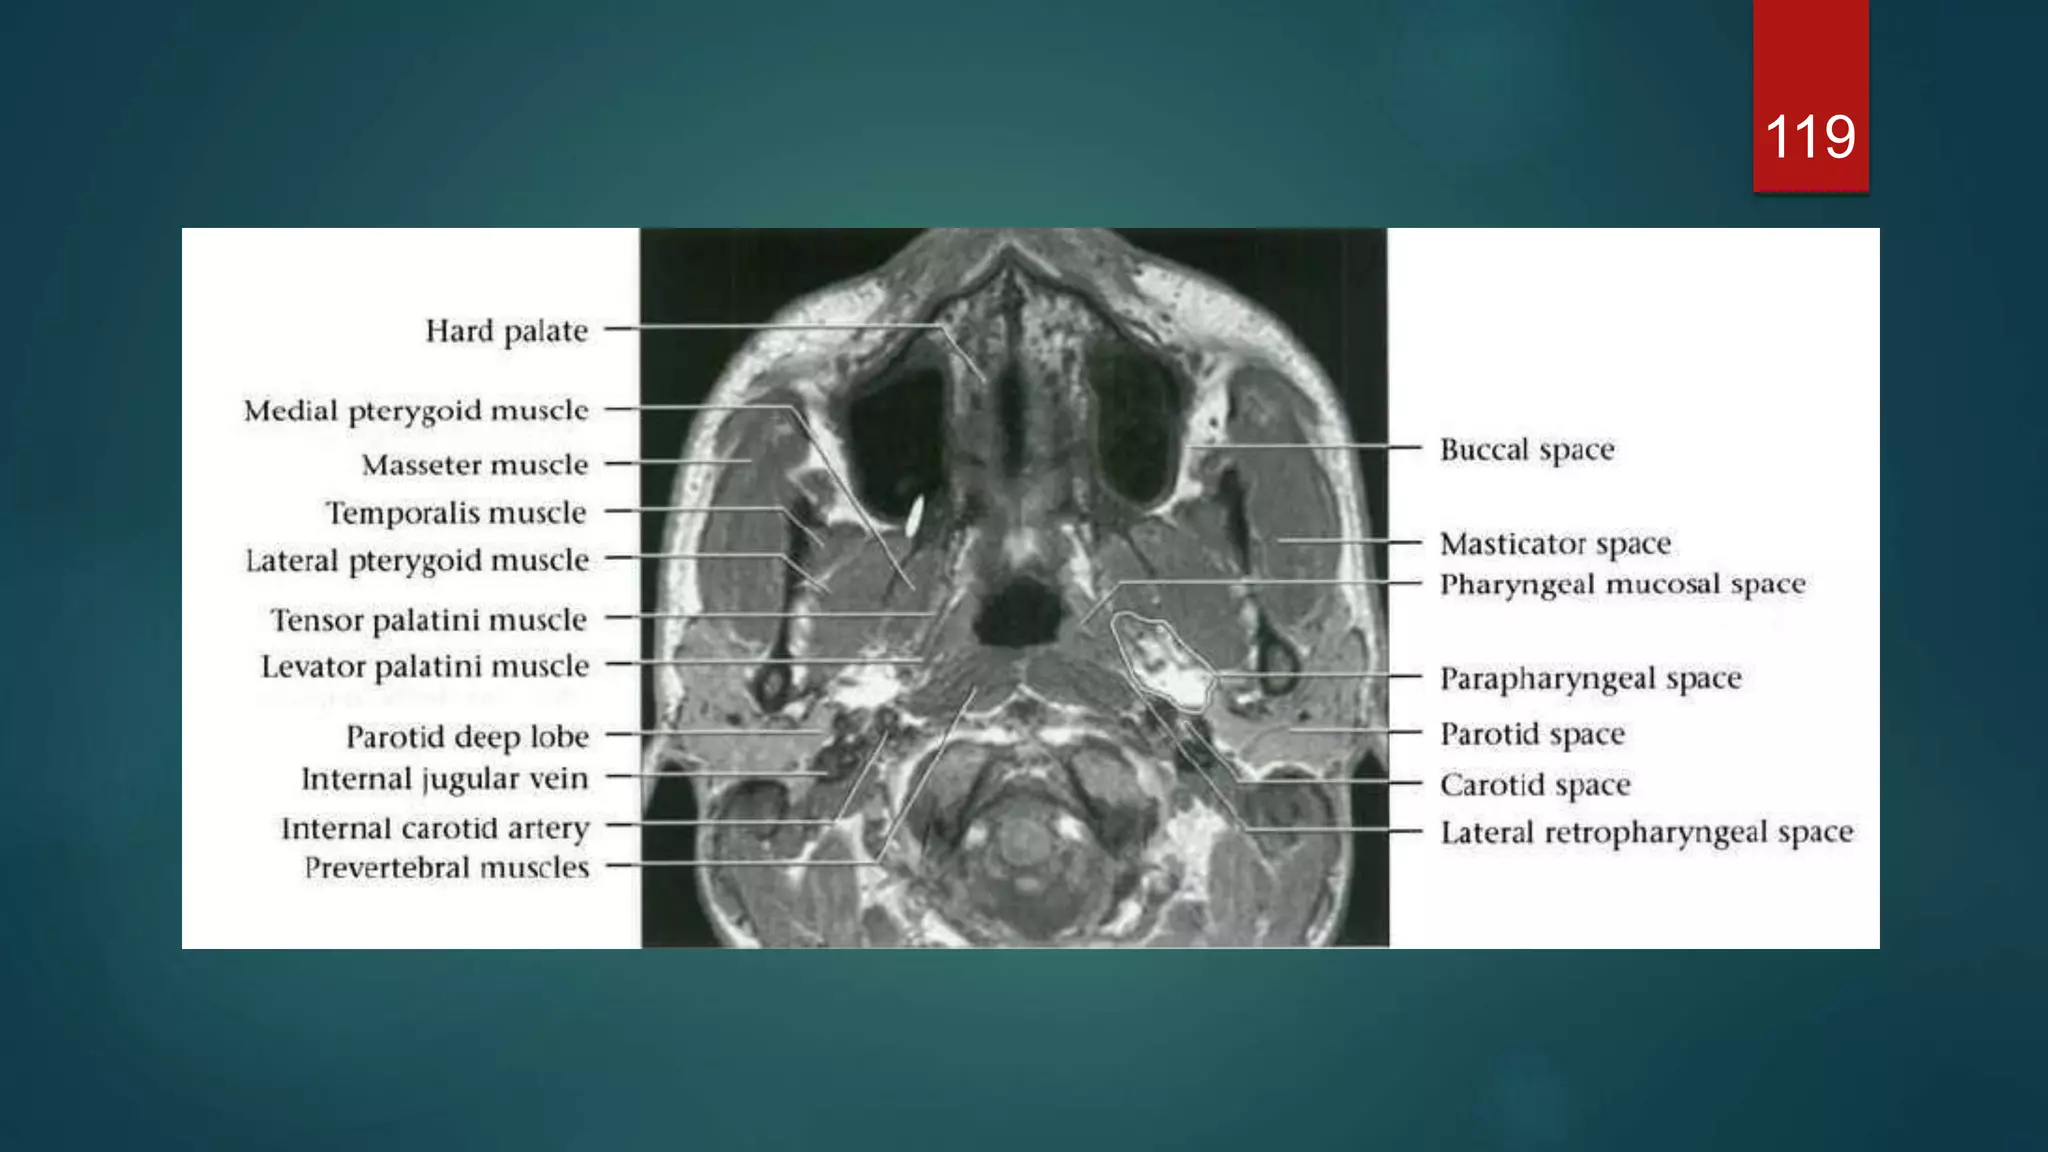

MRI

119